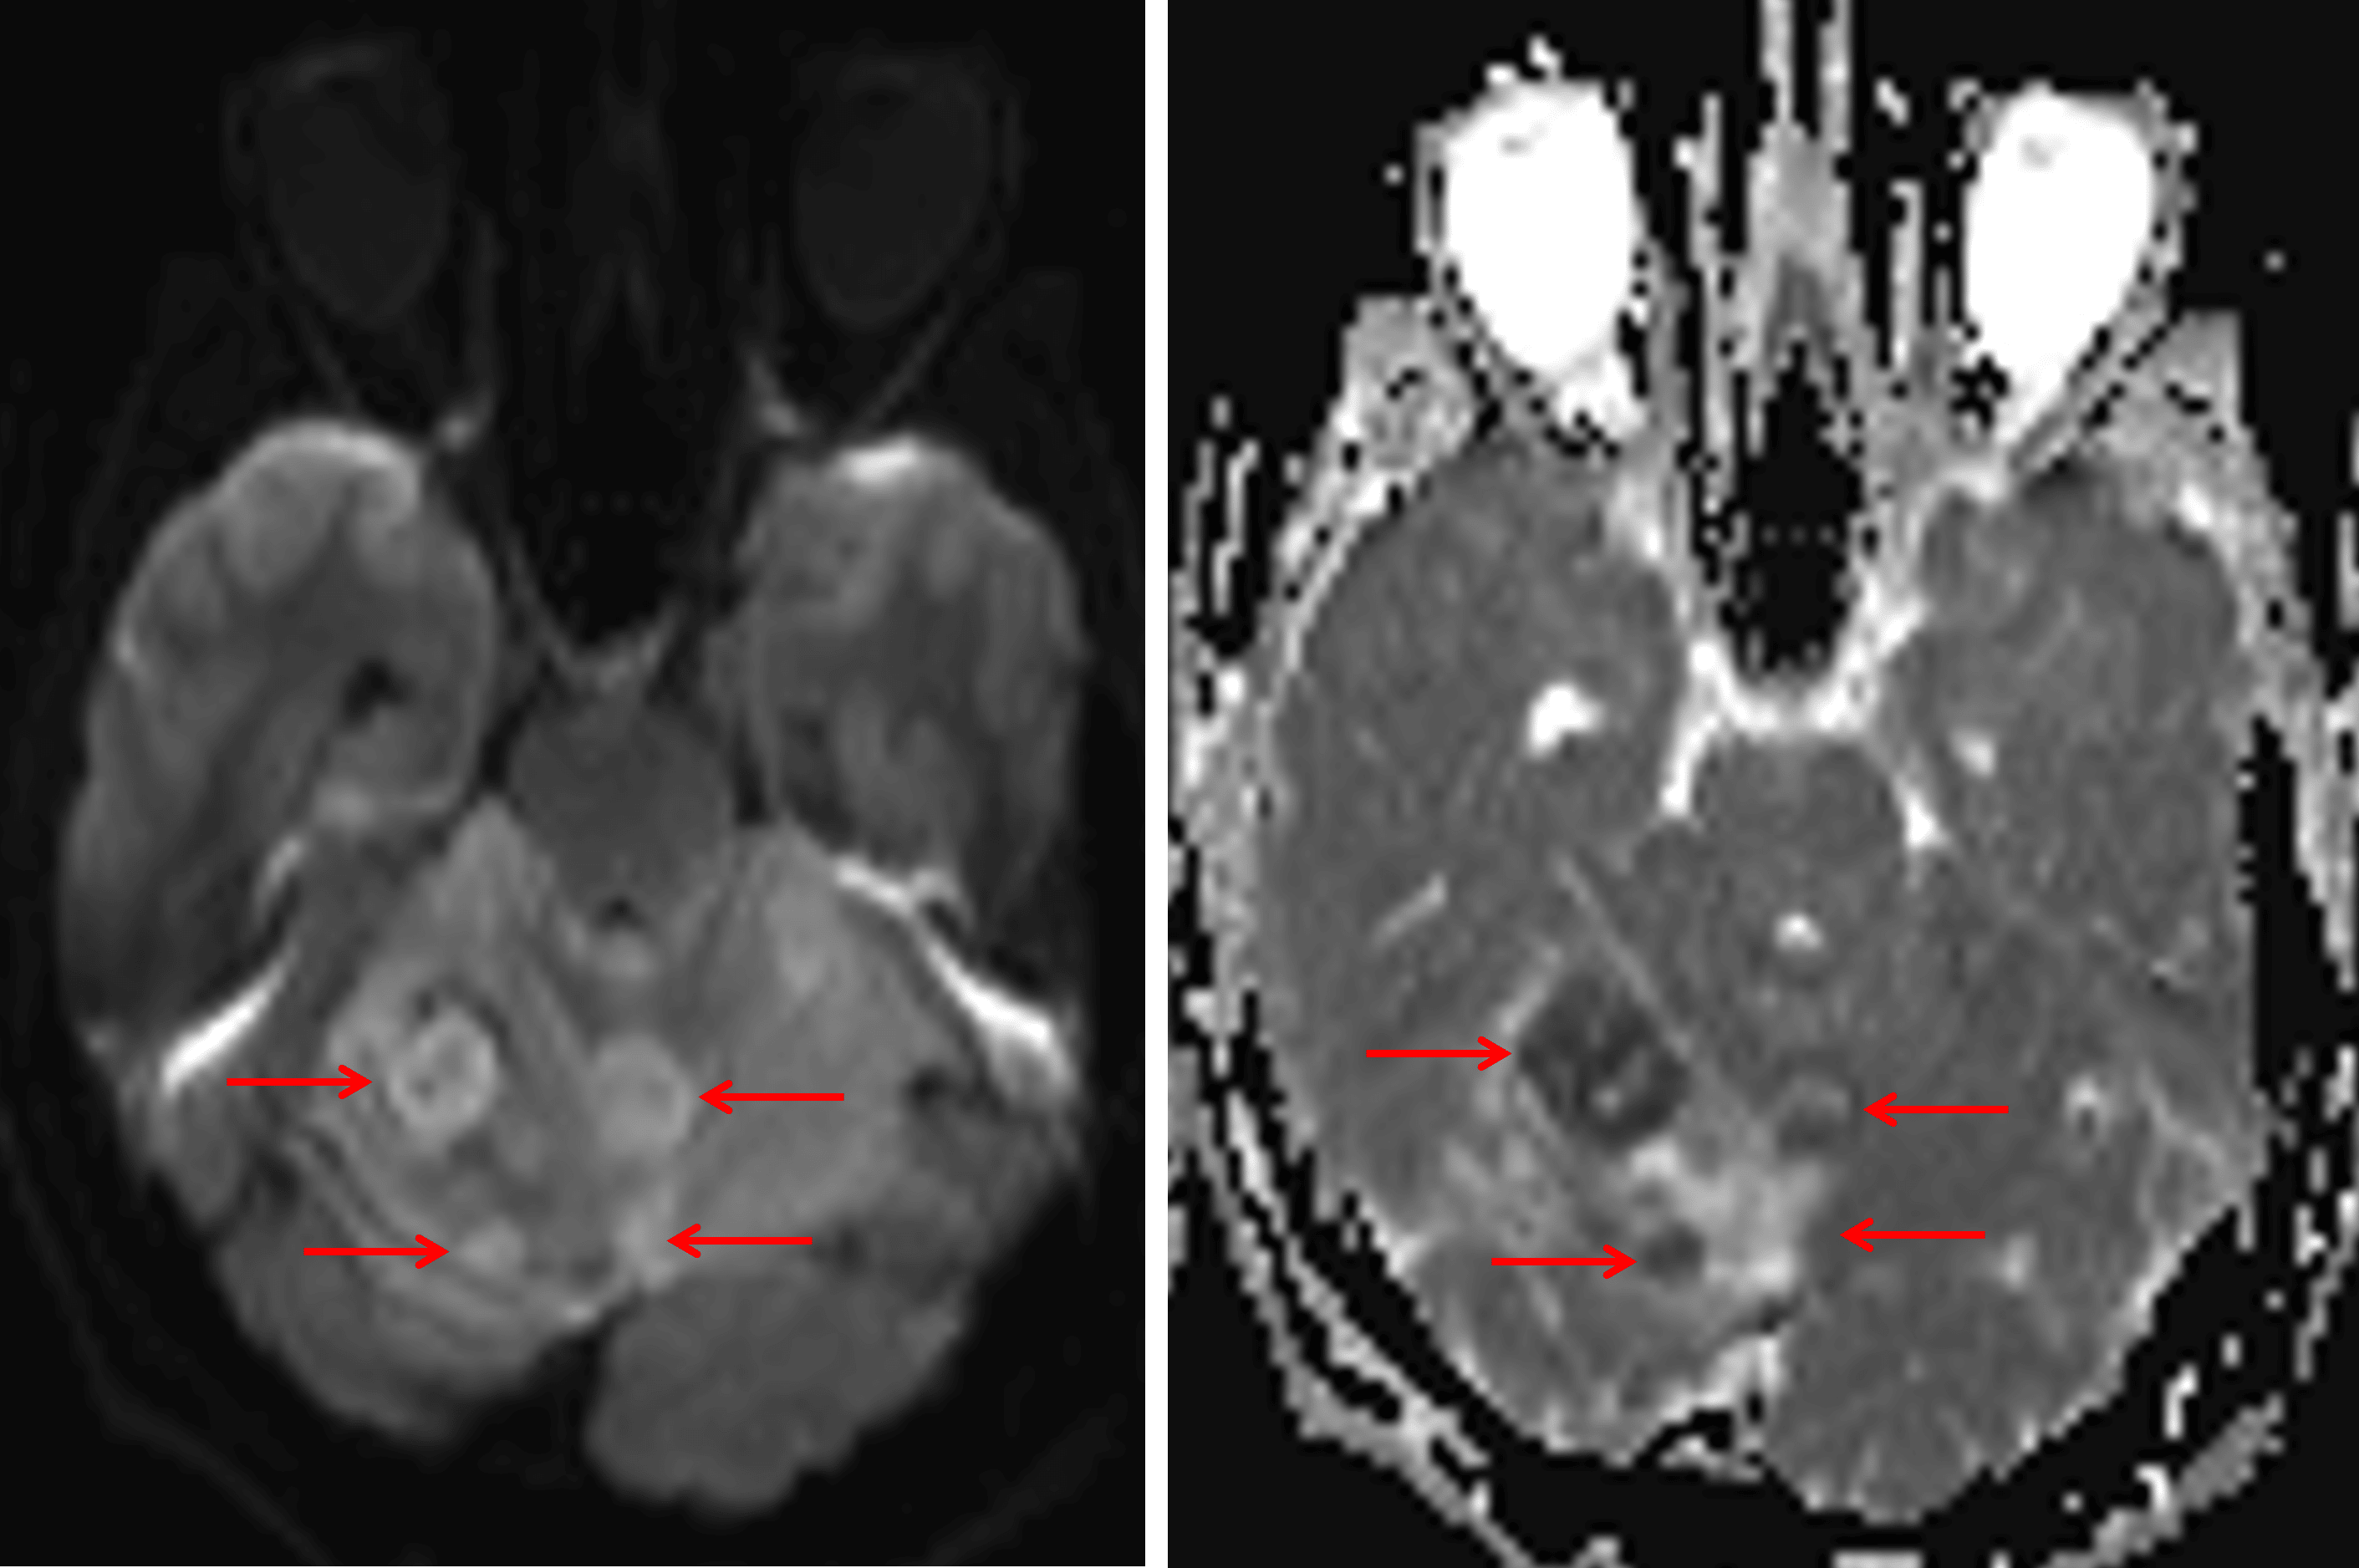

Internal nodular areas of restricted diffusion (red arrows).